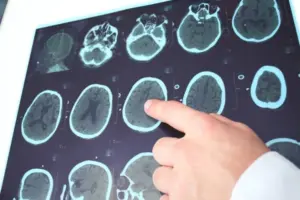

Zánět slepého střeva: 8 příznaků, které byste neměli přehlédnout

Bolest břicha snadno přisoudíme špatnému jídlu nebo nadýmání. Jenže někdy za ní stojí stav, který vyžaduje okamžitou lékařskou pomoc – zánět slepého střeva.